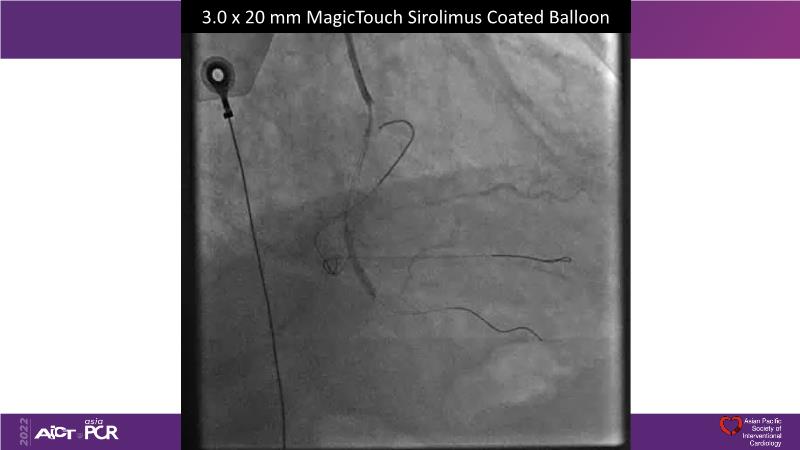

- To understand the technology and scientific evidence of the novel sirolimus drug-coated balloon (SDCB)

- To learn the utility of the DCB for PCI in a variety of lesion and patient subsets